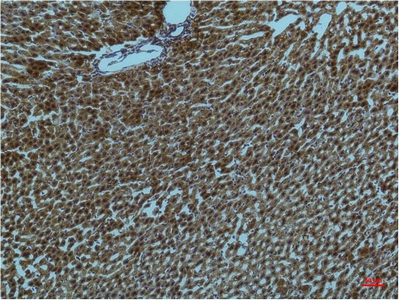

Mouse Monoclonal CytochromeC Antibody

中文名:Cytochrome C抗体

Catalog:IPDX20788

Size: 50μl / 100μl

Application: WB IF IHC ICC FCM Elisa

Reactivity:Human,Mouse,Rat,Chicken

Synonyms:CYCS; CYC; Cytochrome c

Type:Primary antibody